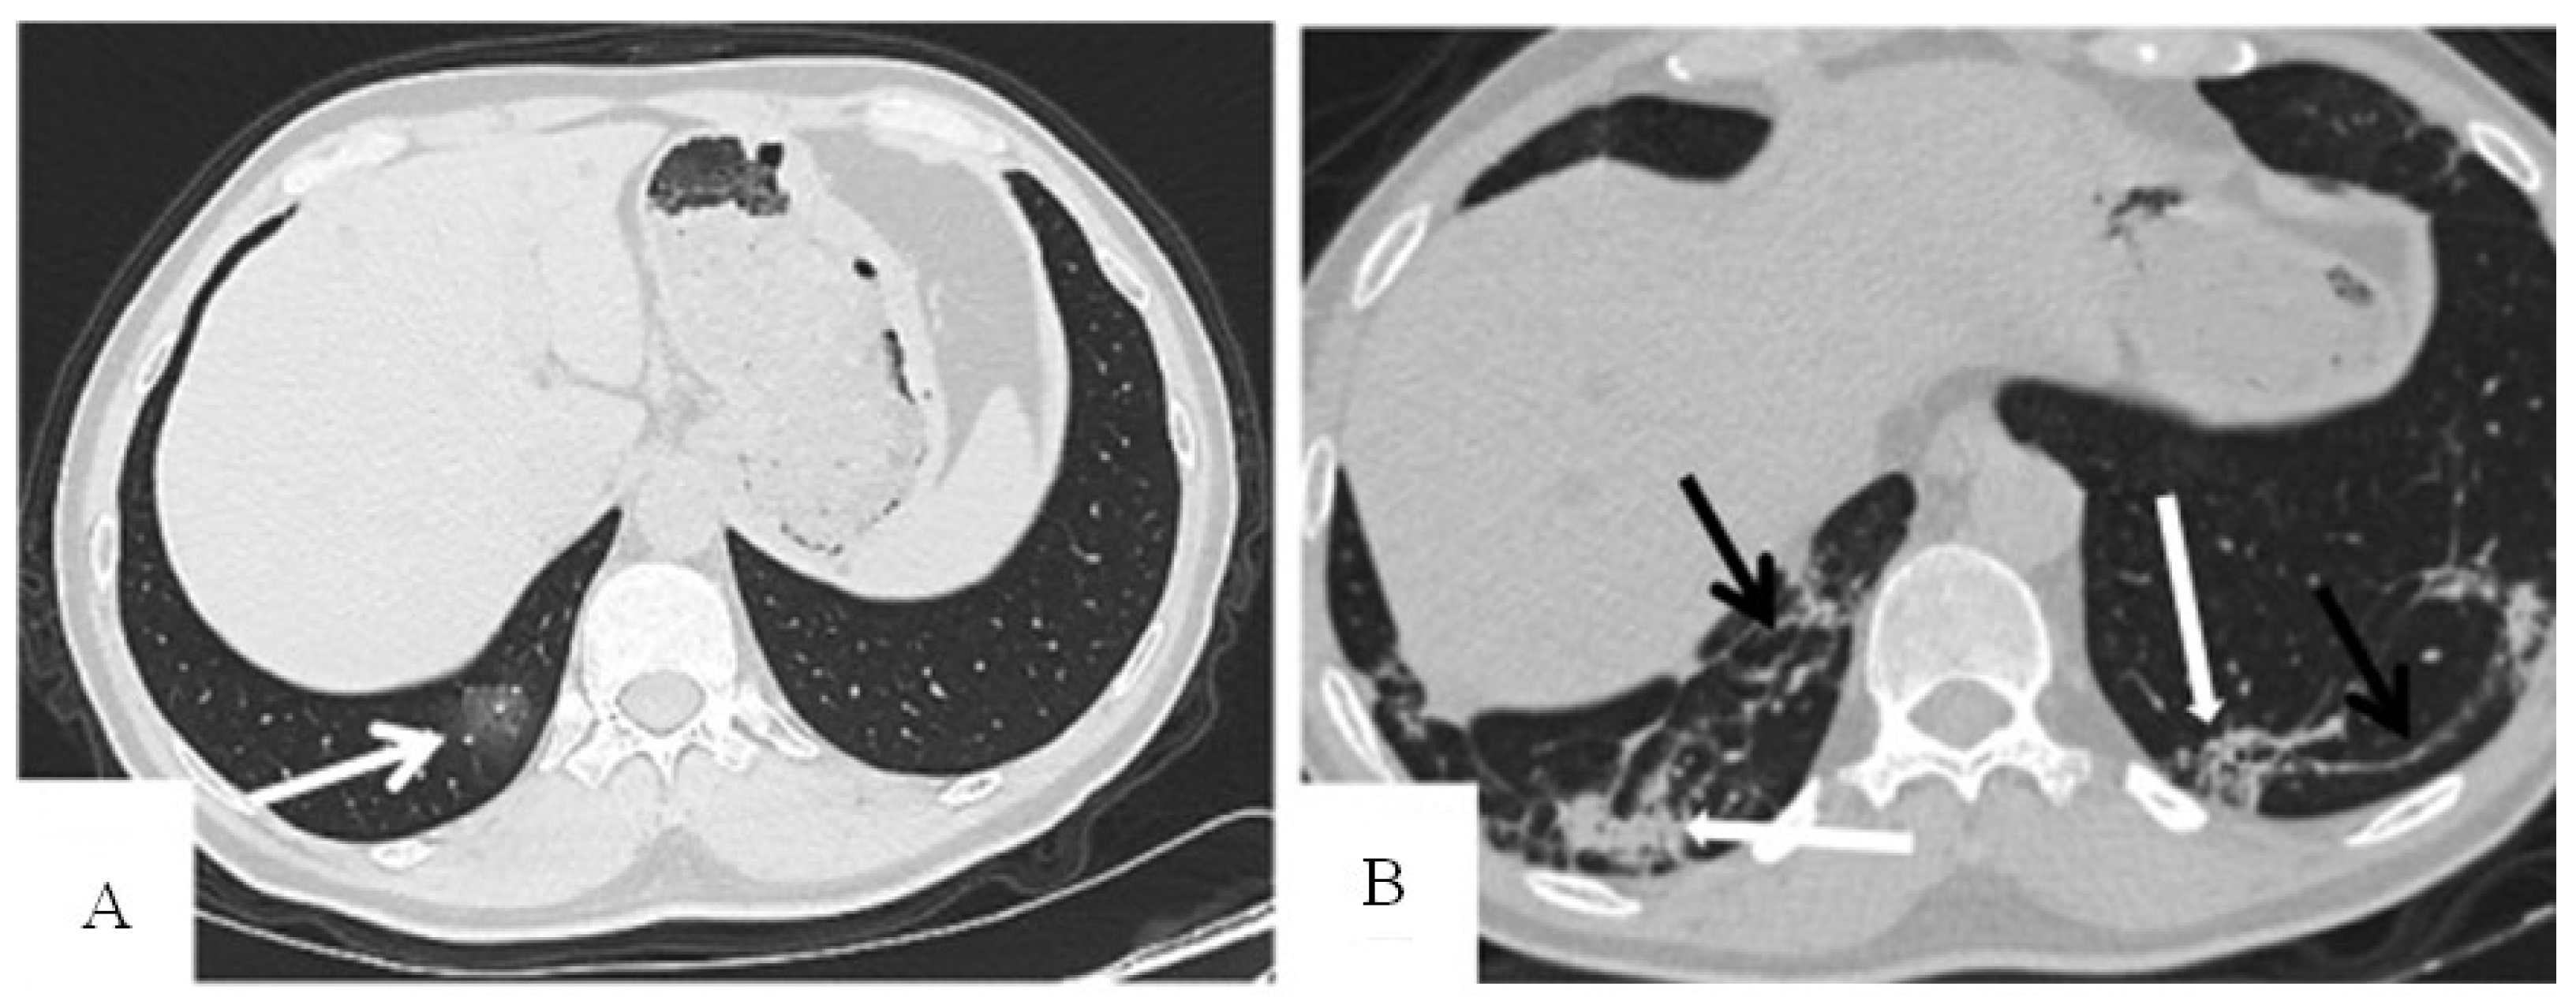

- Define the variables of the explanation set: distribution of pulmonary lesions (no lesion, peripheral, central, diffuse), involvement of the lung (no involvement, single lobe, unilateral multilobe, bilateral multilobe), GGO, crazy-paving pattern, consolidation, linear opacities, air bronchogram, cavitation, bronchiectasis, pleural effusion, pericardial effusion, lymphadenopathy, and pneumothorax.

- Ding, X.; Xu, J.; Zhou, J.; Long, Q. Chest CT Findings of COVID-19 Pneumonia by Duration of Symptoms. Eur. J. Radiol. 2020, 127, 109009. [Google Scholar] [CrossRef] [PubMed]